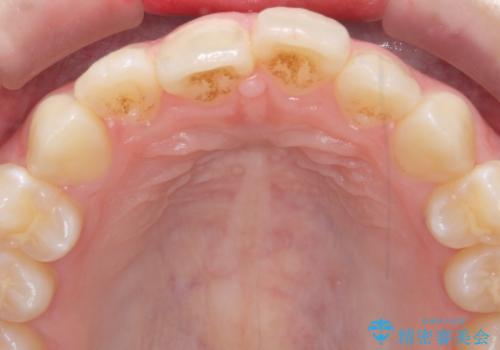

インビザラインライトで行う短期マウスピース矯正治療

- 前歯のガタつきを並べたいたいと、矯正治療を希望され来院されました。

とにかく短期間で前歯だけの治療を行いという希望が強く、全体矯正と前歯だけの部分矯正の仕上がりのイメージを確認したのち14枚のマウスピースで前歯のみの矯正治療を行っていくこととしました。

インビザラインライトは軽度なガタつきや傾斜の改善に用いられる全14枚のマウスピース矯正です。